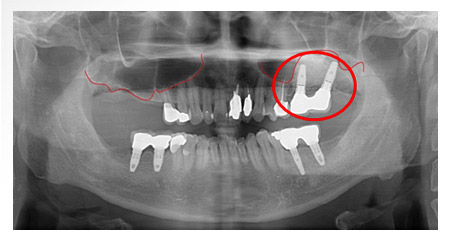

X 光片

術前-標記處骨頭高度不足